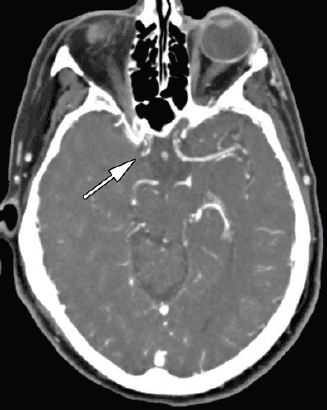

La expansión de la selección por imagen consolida un cambio de paradigma: ya no basta con detectar hipodensidad, oclusión o edema. Hoy se espera que la imagen distinga entre núcleo isquémico establecido, penumbra recuperable y escenarios en los que intervenir puede cambiar el pronóstico funcional del paciente.

El informe radiológico deja de ser una descripción retrospectiva del evento. Ahora define elegibilidad terapéutica, orienta trombólisis o trombectomía en ventanas extendidas, y exige lectura integrada de TAC simple, angioTAC, perfusión y, cuando corresponde, RM multiparamétrica. La interpretación ya no es solo diagnóstica: es estratégica.

En la práctica, esto exige una secuencia operativa clara: TAC sin contraste para descartar hemorragia y detectar signos tempranos, angioTAC para identificar oclusión de gran vaso y estudios de perfusión o RM para valorar tejido recuperable. La calidad del desenlace depende cada vez más de la calidad y velocidad de esa cadena.